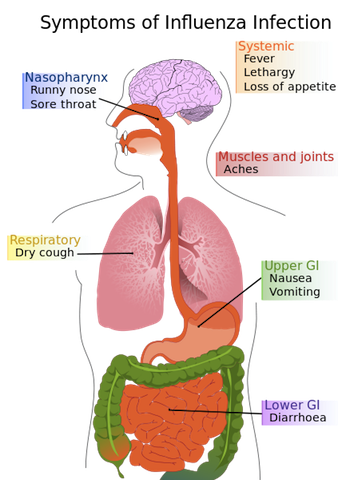

The “Flu” is not a “24 hour stomach bug” or “the stomach flu”

The influenza virus causes an upper respiratory infection with cough, congestion, runny nose, sore throat. Sometimes people can have headache, muscle aches, fatigue and fever. Vomiting and diarrhea does occur sometimes, but this is mostly in children. Symptoms start usually in 1-4 days of exposure, with an average of 2 days. Symptoms can last from a few days to two weeks. (CDC)

There are many influenza viruses.You may have heard of “bird flu” or “swine flu”, specifically H1N1, which had a pandemic outbreak in 2009.

“There are three types of influenza viruses: A, B and C. Human influenza A and B viruses cause seasonal epidemics of disease almost every winter in the United States. The emergence of a new and very different influenza virus to infect people can cause an influenza pandemic. Influenza type C infections cause a mild respiratory illness and are not thought to cause epidemics.

Influenza A viruses are divided into subtypes based on two proteins on the surface of the virus: the hemagglutinin (H) and the neuraminidase (N). There are 17 different hemagglutinin subtypes and 10 different neuraminidase subtypes. Influenza A viruses can be further broken down into different strains. Current subtypes of influenza A viruses found in people are influenza A (H1N1) and influenza A (H3N2) viruses. In the spring of 2009, a new influenza A (H1N1) virus (CDC 2009 H1N1 Flu website) emerged to cause illness in people. This virus was very different from regular human influenza A (H1N1) viruses and the new virus caused the first influenza pandemic in more than 40 years. That virus (often called “2009 H1N1”) has now mostly replaced the H1N1 virus that was previously circulating in humans.” (CDC)